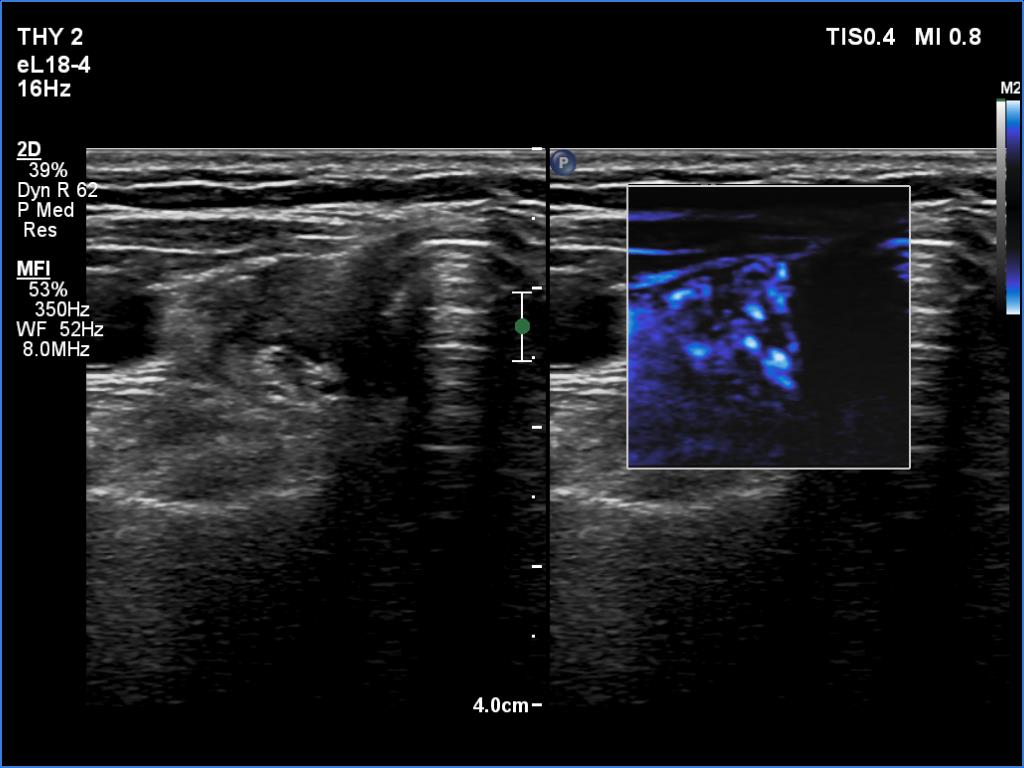

The operated thyroid - case 1563 (ultrasonographic picture 4)

Right lobe, transverse scan, microflow imaging. The lobe has numerous vessels.